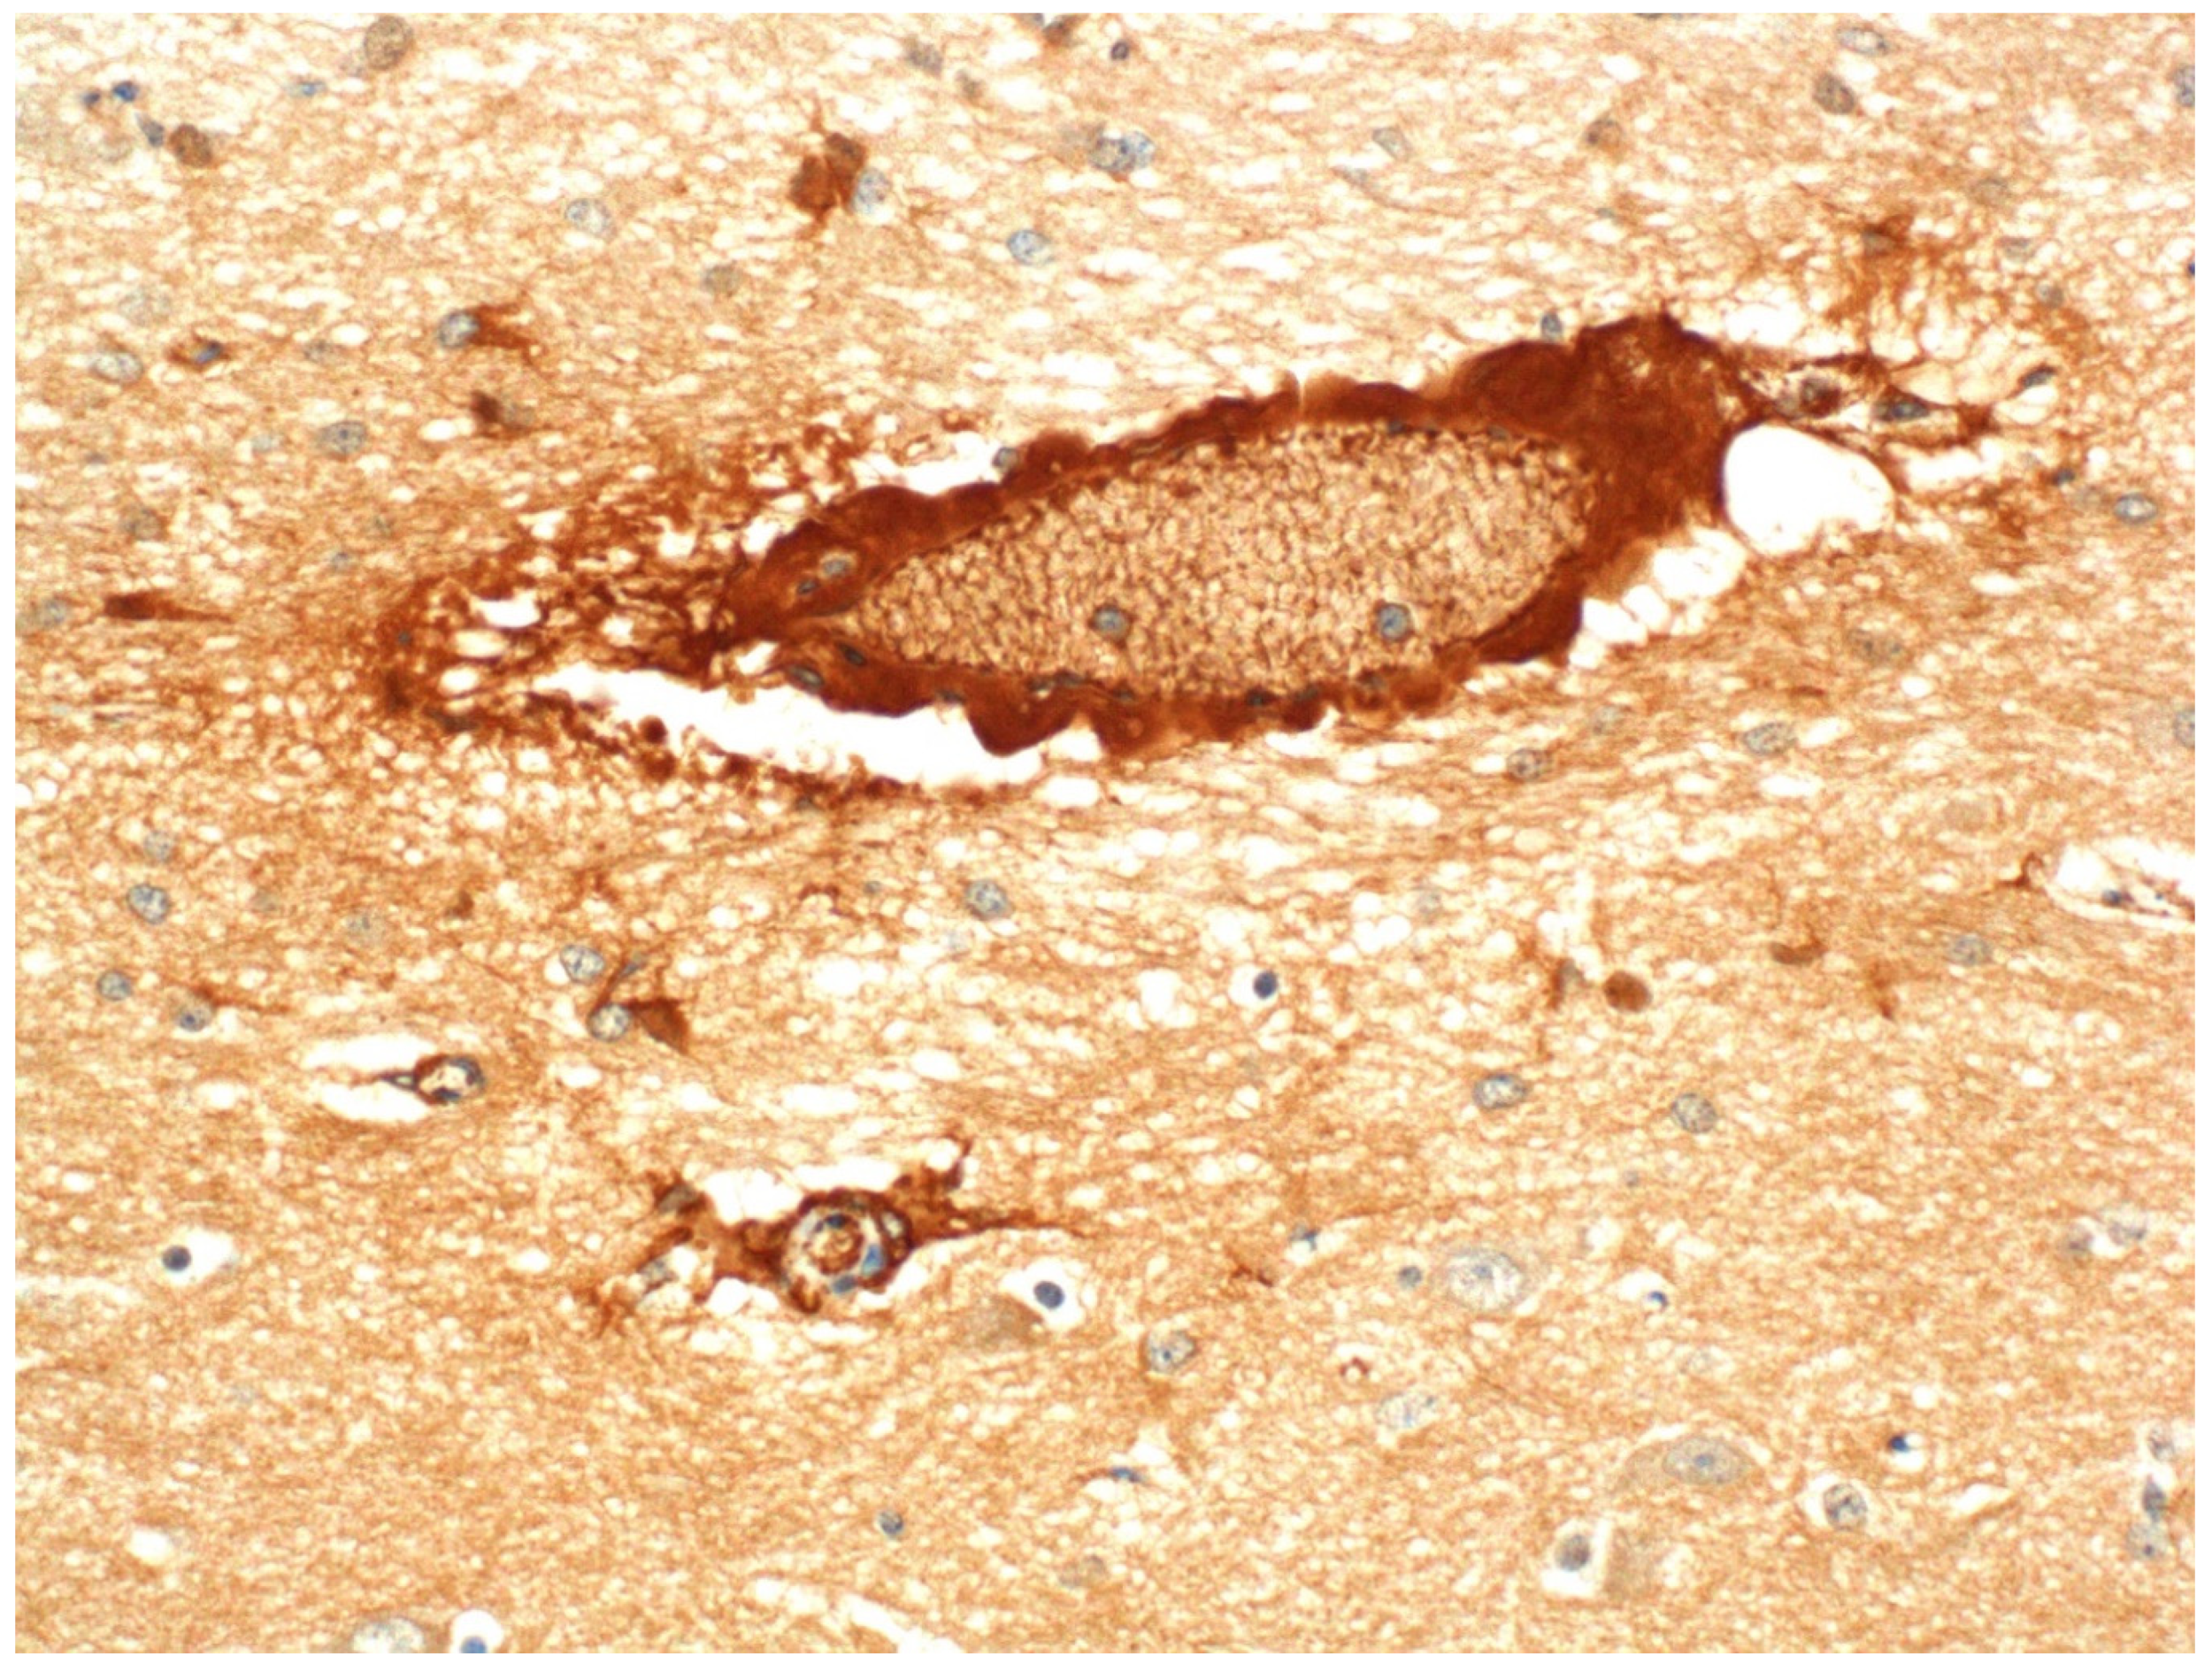

- Finnie, J.W.; Manavis, J.; Blumbergs, P.C. Aquaporin-4 in acute cerebral edema produced by Clostridium perfringens type D epsilon toxin. Vet. Pathol. 2008, 45, 307–309. [Google Scholar] [CrossRef] [PubMed]

- Finnie, J.W.; Manavis, J.; Chidlow, G. Loss of endothelial barrier antigen (EBA) immunoreactivity as a marker of Clostridium perfringens type D epsilon toxin-induced microvascular damage in rat brain. J. Comp. Pathol. 2014, 151, 153–156. [Google Scholar] [CrossRef]

- Zhu, C.; Ghabriel, M.N.; Blumbergs, P.C.; Reilly, P.L.; Manavis, J.; Youssef, J.; Hatami, S.; Finnie, J.W. Clostridium perfringens prototoxin-induced alteration of endothelial barrier antigen (EBA) immunoreactivity at the blood-brain barrier (BBB). Exp. Neurol. 2001, 169, 72–82. [Google Scholar] [CrossRef]